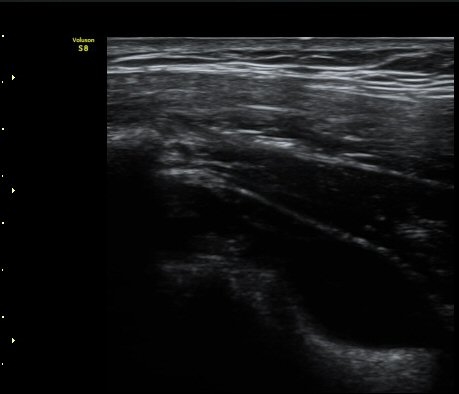

3°³¿ù ÈÄ ÃßÀû°Ë»ç

2049205267_e81a53aa_US181338113.jpg